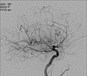

Die Röntgenaufnahmen zeigen die mechanische Rekanalisation (Thrombektomie) eines akuten Verschlusses der inneren Halsschlagader auf der linken Seite (Abb. 1-10).

Zunächst wird der Verschluss angiografisch dargestellt (Abb. 1 und 2). Anschließend wird ein Mikrokatheter durch den verschlossenen Gefäßabschnitt bis hinter das Gerinnsel navigiert (Abb. 3) und das Gefäß erneut dargestellt (Abb. 4). Als Nächstes wird ein sog. Stentretriever aus dem Mikrokatheter über dem Gerinnsel freigesetzt (Abb. 5 und 6). Der Stentretriever ermöglicht einen temporären Blutfluss (Abb. 7) (Bypassfunktion). Abschließend wird der Stentretriever mit dem darin verfangenen Gerinnsel unter Aspiration über den Absaugkatheter entfernt (Abb. 8). Die abschließenden Kontrollaufnahmen zeigen eine vollständige Beseitigung des Gerinnsels und eine freie Durchgängigkeit des Gefäßes (Abb. 9 und10).